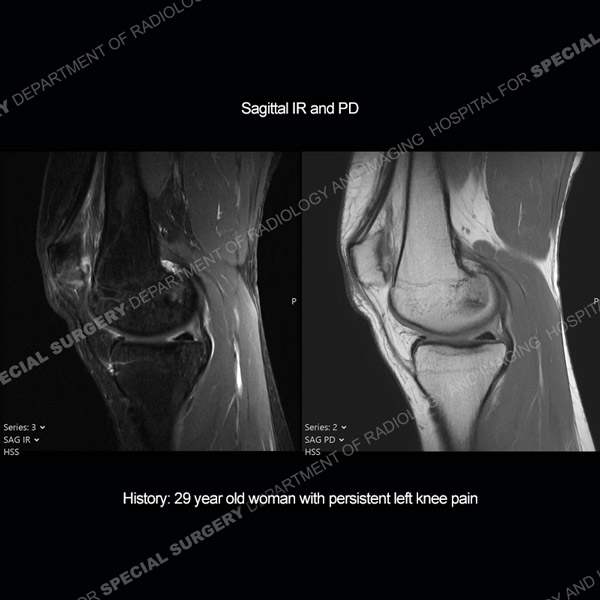

Featured Case of the MonthCase 216: 29-year-old woman with persistent left knee pain.